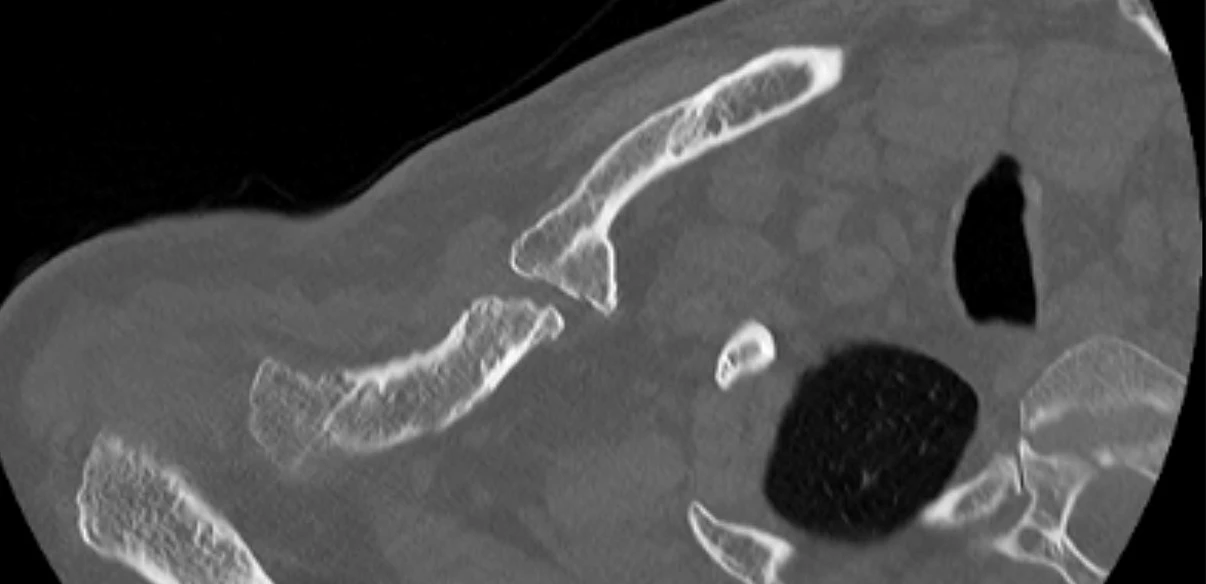

Subsequent imaging confirmed an established hypertrophic non-union of the right clavicle. CT scans and preoperative planning were arranged to assess the feasibility of surgical correction with bone grafting to restore clavicular length. A careful plan was put forward to possibly take down his nonunion, bone graft the defect and replate the clavicle.

This was all done with 3D CT imaging.

Pre op CT 1 showing site of non union

Pre op CT 2 showing site of non union